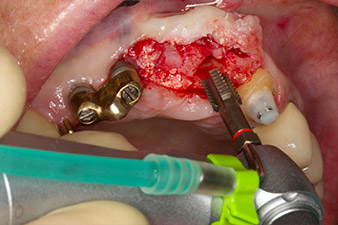

Dopo la prima guarigione, i tessuti molli sono stati sagomati con un ponte rivestito nella porzione basale. Due mesi dopo, il sito è stato esposto con una leggera incisione sula cresta palatoalveolare (Fig. 2). Si è visto che le dimensioni dell'osso alveolare erano sufficienti in corrispondenza della posizione 22. Le figure 2 e 4 mostrano la preparazione della sede di impianto, l'avvitamento e l'impianto utilizzando Implantmed.

Il nuovo motore per implantologia è stato utilizzato con i manipoli chirurgici contrangoli W&H appropriati.

Per compensare la perdita ossea periodontale e ottenere un risultato estetico piacevole, si è proceduto all'impianto unitamente alla rigenerazione guidata dell'osso (tecnica GBR) con materiale di riempimento xenogenico e membrana di collagene (Fig. 5 e 6).